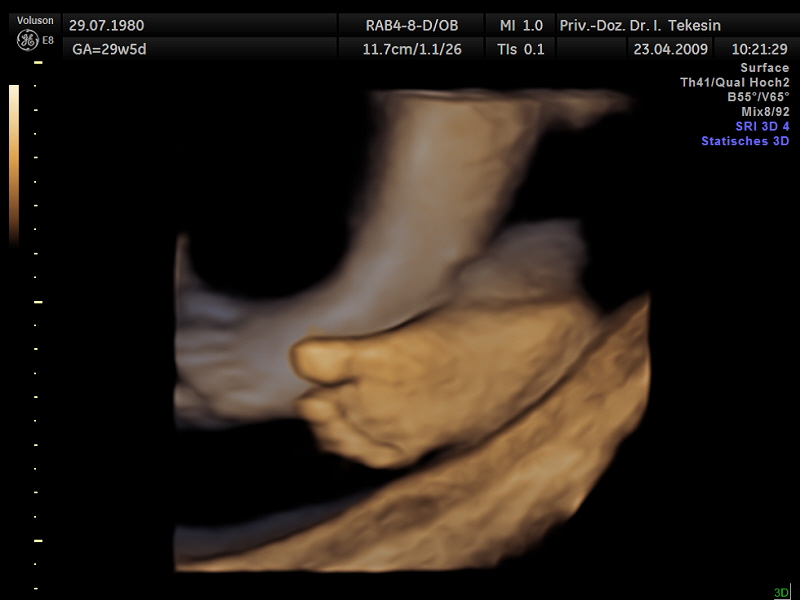

3D-/4D-Ultraschall (optional)

Immer mehr werdende Eltern interessieren sich für die faszinierenden Bilder, die dieses Verfahren liefert. Die plastische, dreidimensionale Darstellung der Oberfläche des Gesichts und anderer Körperregionen wird durch spezielle Bildrekonstruktion in schnellen Rechnern erreicht. Auch einzelne innere Organe oder „Gefäßbäume“ können von allen Seiten betrachtet werden. Viele dünne Schnittebenen (2D) werden zu einer gemeinsamen 3D-Sichtweise im Computer des Ultraschallgerätes zusammengeführt. Unter einem 4D-Ultraschall versteht man darüber hinaus eine 3D-Ultraschalluntersuchung unter Echtzeitbedingungen. Anstatt nur statische Bilder anzuzeigen, erfasst ein 4D-Ultraschall die Bewegungen des Kindes, weshalb er auch als „Live-3D-Ultraschall“ bezeichnet wird.

Diese Vorgehensweise ermöglicht äußerst realistische Bilder, bei denen sogar Gestik und Mimik des Kindes in bewegten Sequenzen festgehalten werden können. Die Untersuchung kann wie auch der normale Ultraschall während des gesamten Schwangerschaftszeitraums durchgeführt werden. Möchte man das Ungeborene komplett sehen, wird die 12. bis 16. Schwangerschaftswoche empfohlen, die Zeit zwischen der 28. und 33. Schwangerschaftswoche eignet sich besonders zur präzisen Darstellung einzelner Körperteile

Ein Fuß

Ein Fuß (3D-Darstellung)